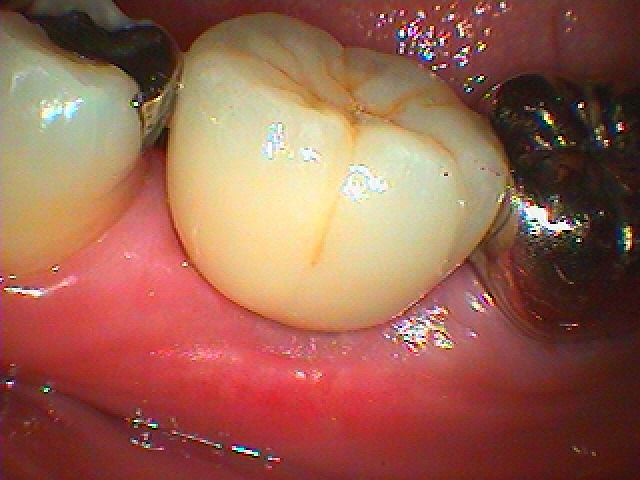

インプラント部の上部構造の作成 オールセラミックにて機能回復していきます|お知らせ |広島市安佐南区の歯科医院 インプラント部の上部構造の作成 オールセラミックにて機能回復していきます トップ お知らせ・ブログ お知らせ インプラント部の上部構造の作成 オールセラミックにて機能回復していきます インプラント部の上部構造の作成 オールセラミックにて機能回復していきます 2か月後になります 歯肉形態を作成しています 作成したオールセラミックになります このような形態にて作成しています 口腔内にて合わせたところになります デンタルレントゲンになります 埋入時のパノラマになります Web診療予約 初めての方へ 選ばれ続ける理由 院内設備について 歯が痛いしみる一般歯科 歯がぐらぐらする歯周病 健康な歯を保ちたい予防歯科 子供の虫歯予防をしたい小児歯科 銀歯をセラミックに審美歯科 白い歯を目指しませんか?ホワイトニング 矯正専門医がいるので安心矯正歯科 抜けた歯を補いたいインプラント・入れ歯 医院案内 スタッフ紹介 メリィハウス歯科クリニックオフィシャルホームページ ラベンダー歯科クリニックオフィシャルホームページ お知らせ・ブログ ホーム 診療科目 一般歯科 歯周病治療 予防治療 小児歯科 審美治療 ホワイトニング 矯正歯科 入れ歯・インプラント マウスピース矯正 初めての方へ 院長・スタッフ 設備紹介 医院案内・アクセス メニューを閉じる